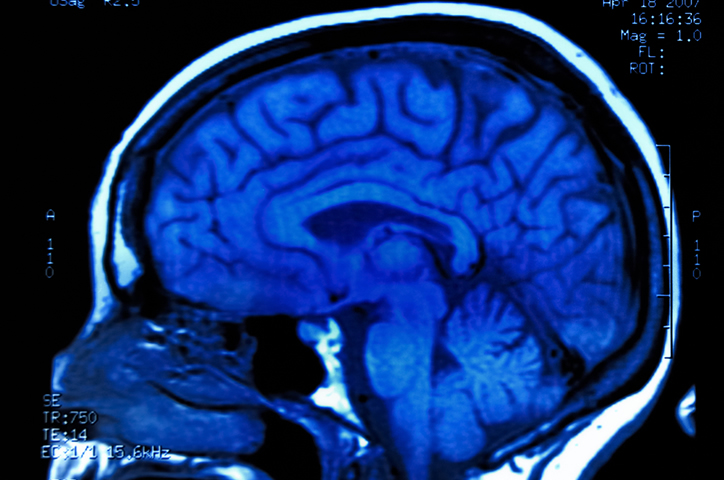

When malignant (cancerous) cells arise in the brain tissue to form a tumor, this disease is referred to as brain cancer. Usually, these tumors will grow enough to interfere with essential brain functions including memory, sensations, and muscle control. Other, non-cancerous tumors can develop in the brain as well—these...